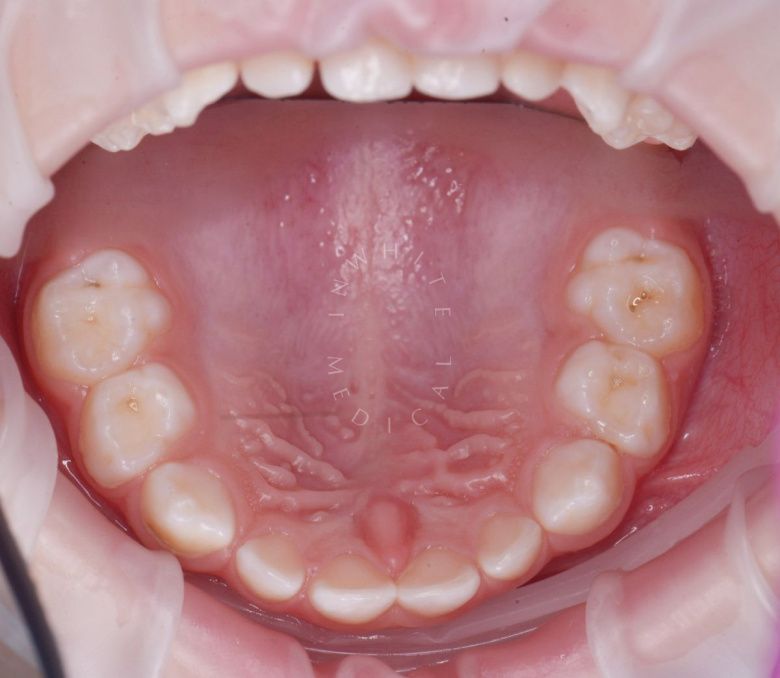

етская стоматология под наркозом Москва. Лечение молочных зубов и установка металлических коронок во сне - до процедуры